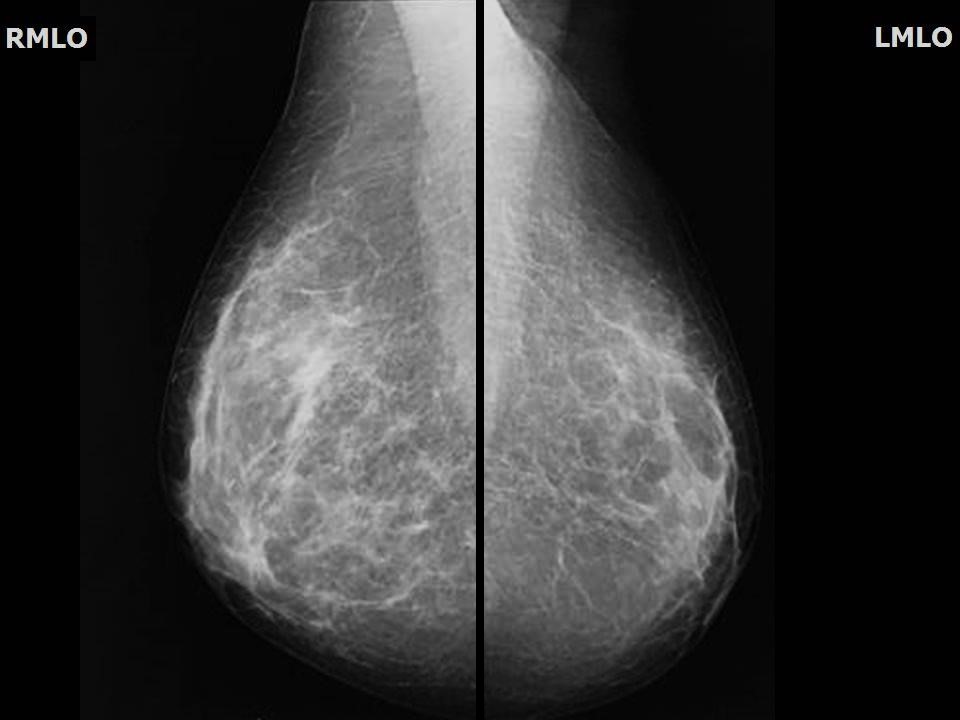

Феномен гипердиагностики в маммографии: примеры и иллюстрации

Раздел: Образы вокруг